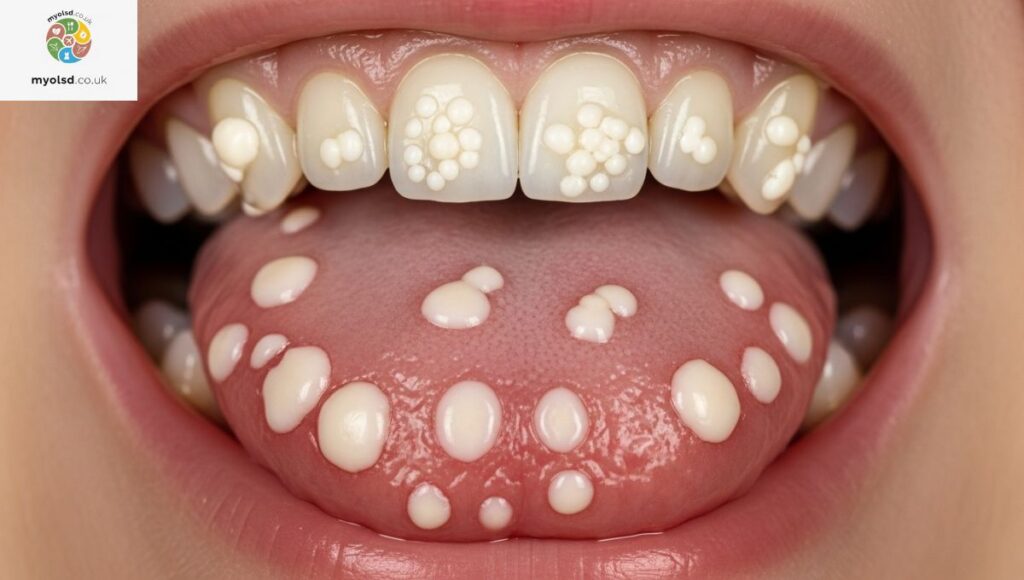

5. Oral Thrush

If your roof of mouth pain feels more like a burning sensation and you notice white patches, it might be oral thrush, a yeast infection caused by Candida albicans. This condition is more common if you use inhalers, take antibiotics, or have diabetes.

Thrush can make eating uncomfortable and cause a metallic taste in your mouth. Antifungal treatments like Diflucan or medicated mouthwashes can help clear it up. Keeping your mouth clean and staying hydrated also helps prevent recurrence.

6. Squamous Papilloma (Warts)

Sometimes, a small wart-like bump called squamous papilloma can form on the roof of your mouth. It’s usually caused by the HPV virus and isn’t painful, but if irritated by food or dental appliances, it can cause discomfort while eating.

Treatment may involve cryotherapy, laser therapy, or surgical removal, depending on the size and location. While most are benign, it’s best to have your dentist check any unusual growth in your mouth.